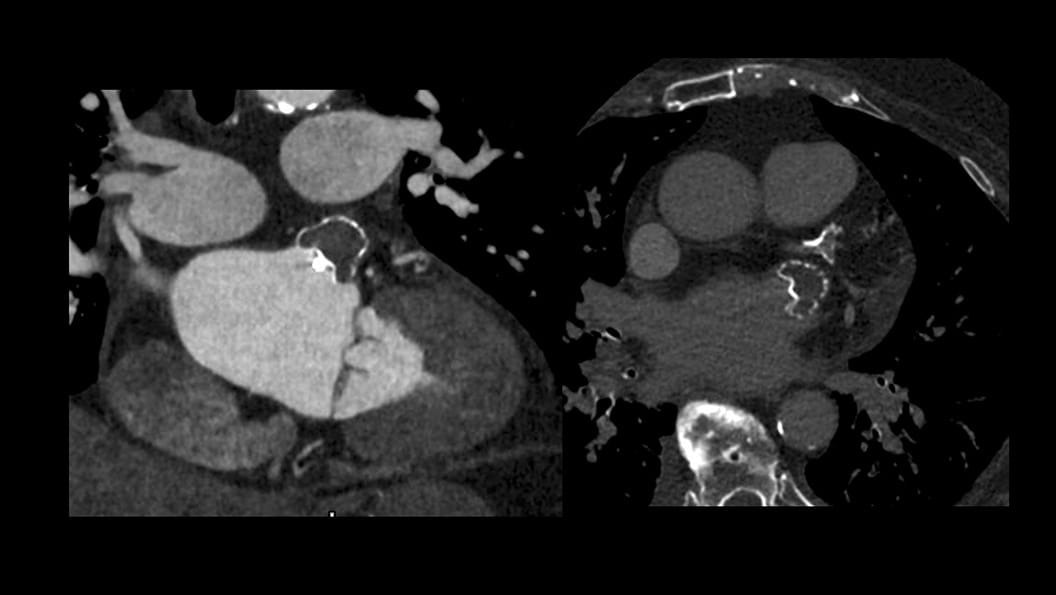

CT-Guided Interventional Care

Since becoming an important step in the patient care pathway and heart care guidelines, CT images are an invaluable tool in the cath lab, guiding procedures for precise personalized care.